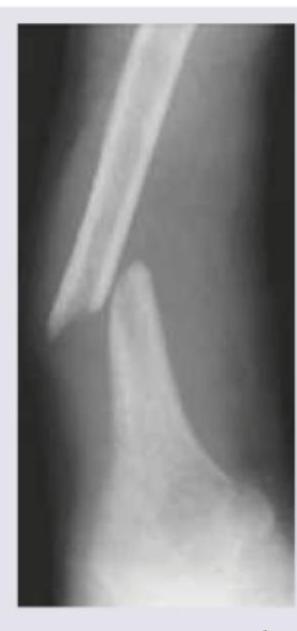

The X-ray was taken 8 weeks after sustaining fracture. What is the diagnosis?

Explanation: ***Nonunion*** - The X-ray image shows a clear **gap** between the two bone fragments, and the bone ends appear **sclerotic** and rounded, indicating that the bone has failed to heal after 8 weeks. - Nonunion is the failure for a fracture to heal after a reasonable period, often defined by the absence of signs of healing for 3-6 months depending on the bone and site, but after 8 weeks with clearly visible sclerotic fragment ends suggests this condition. *Malunion* - **Malunion** occurs when a fracture heals, but in a **deformed** or anatomically incorrect position, which is not evident in the provided image as the fragments are still separate. - The primary problem here is the *absence* of healing, not the healing in a misaligned fashion. *Myositis ossificans* - **Myositis ossificans** is the formation of **heterotopic bone** within muscle or soft tissue, typically following trauma, and would appear as calcification *outside* the bone shaft. - The image clearly depicts unhealed bone fragments, not new bone formation within surrounding soft tissues. *Avascular necrosis* - **Avascular necrosis** (AVN) is the death of bone tissue due to interruption of blood supply, often leading to **collapse of the bone**, which is usually seen in particular bones like the femoral head or scaphoid. - While AVN can complicate fractures, the image primarily shows a lack of bony bridging rather than changes indicative of bone death and collapse.